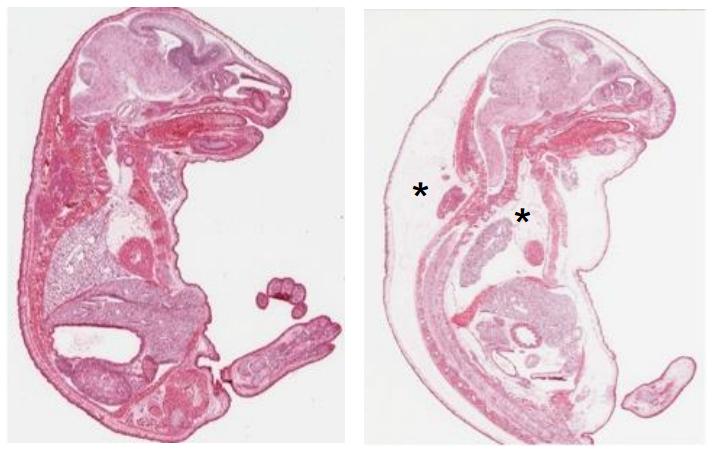

Osaka University-led Japanese researchers have now identified a protein that is crucial for this lymphatic system remodeling and maturation. Polydom is a large protein known to interact with the receptor integrin α9β1, and is found in the extracellular matrix surrounding and supporting cells. The research team found that mice genetically engineered to lack Polydom died immediately after birth because they had lung edema, which prevented them from breathing. Further investigation revealed that a primitive lymphatic system developed in these mice, but branching vessels failed to grow and the mature vasculature did not form, leading to fluid accumulation in tissues. Genetically engineered zebrafish lacking Polydom also exhibited a failure of lymph vessel development.

The team then explored the location of Polydom in mice, and found that the protein associates with lymphatic vessels throughout embryonic development.